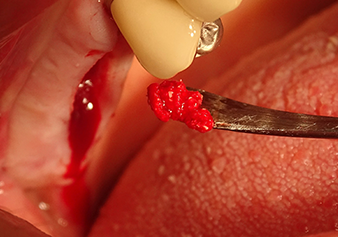

The I2A instrument (diameter 2.0 mm) was then used to perforate the sinus floor intermittently and on the smallest scale possible. This special piezosurgical method ensures that the Schneiderian membrane is not damaged. When the Z25P was used, the membrane was already lifted slightly by the coolant supplied via the instrument tip (Fig. 3). The coolant quantity was just 50% in order to avoid high pressure in the implant bed.

The Schneiderian membrane is carefully detached with the Z25P instrument (phase 1)

Fig.3: Following marking of the implant position and initial expansion of the bed, the Schneiderian membrane is carefully detached with the Z25P instrument (phase 1).